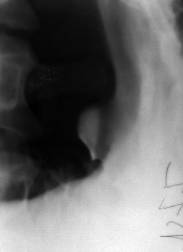

Stomacul este dilatat si prezinta unde peristaltice adânci, frecvente, ineficiente. Evacuarea este încetinita. Canalul piloric este îngustat alungit de 1-2 cm, având aspect de pilor în paranteze sprijinite, de pilor între paranteze când muschiul piloric protrude în baza bulbului duodenal sau în antru, sau pilor în duble paranteze.